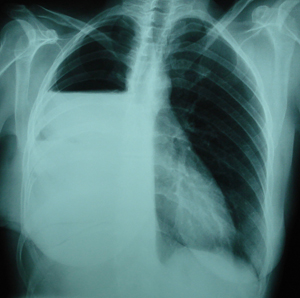

Εικόνα 1

Οπισθιοπροσθία ακτινογραφία του θώρακος. Διακρίνεται ευμεγέθης σκίαση στο μέσο πνευμονικό πεδίο του δεξιού πνεύμονος, με ομαλά όρια.